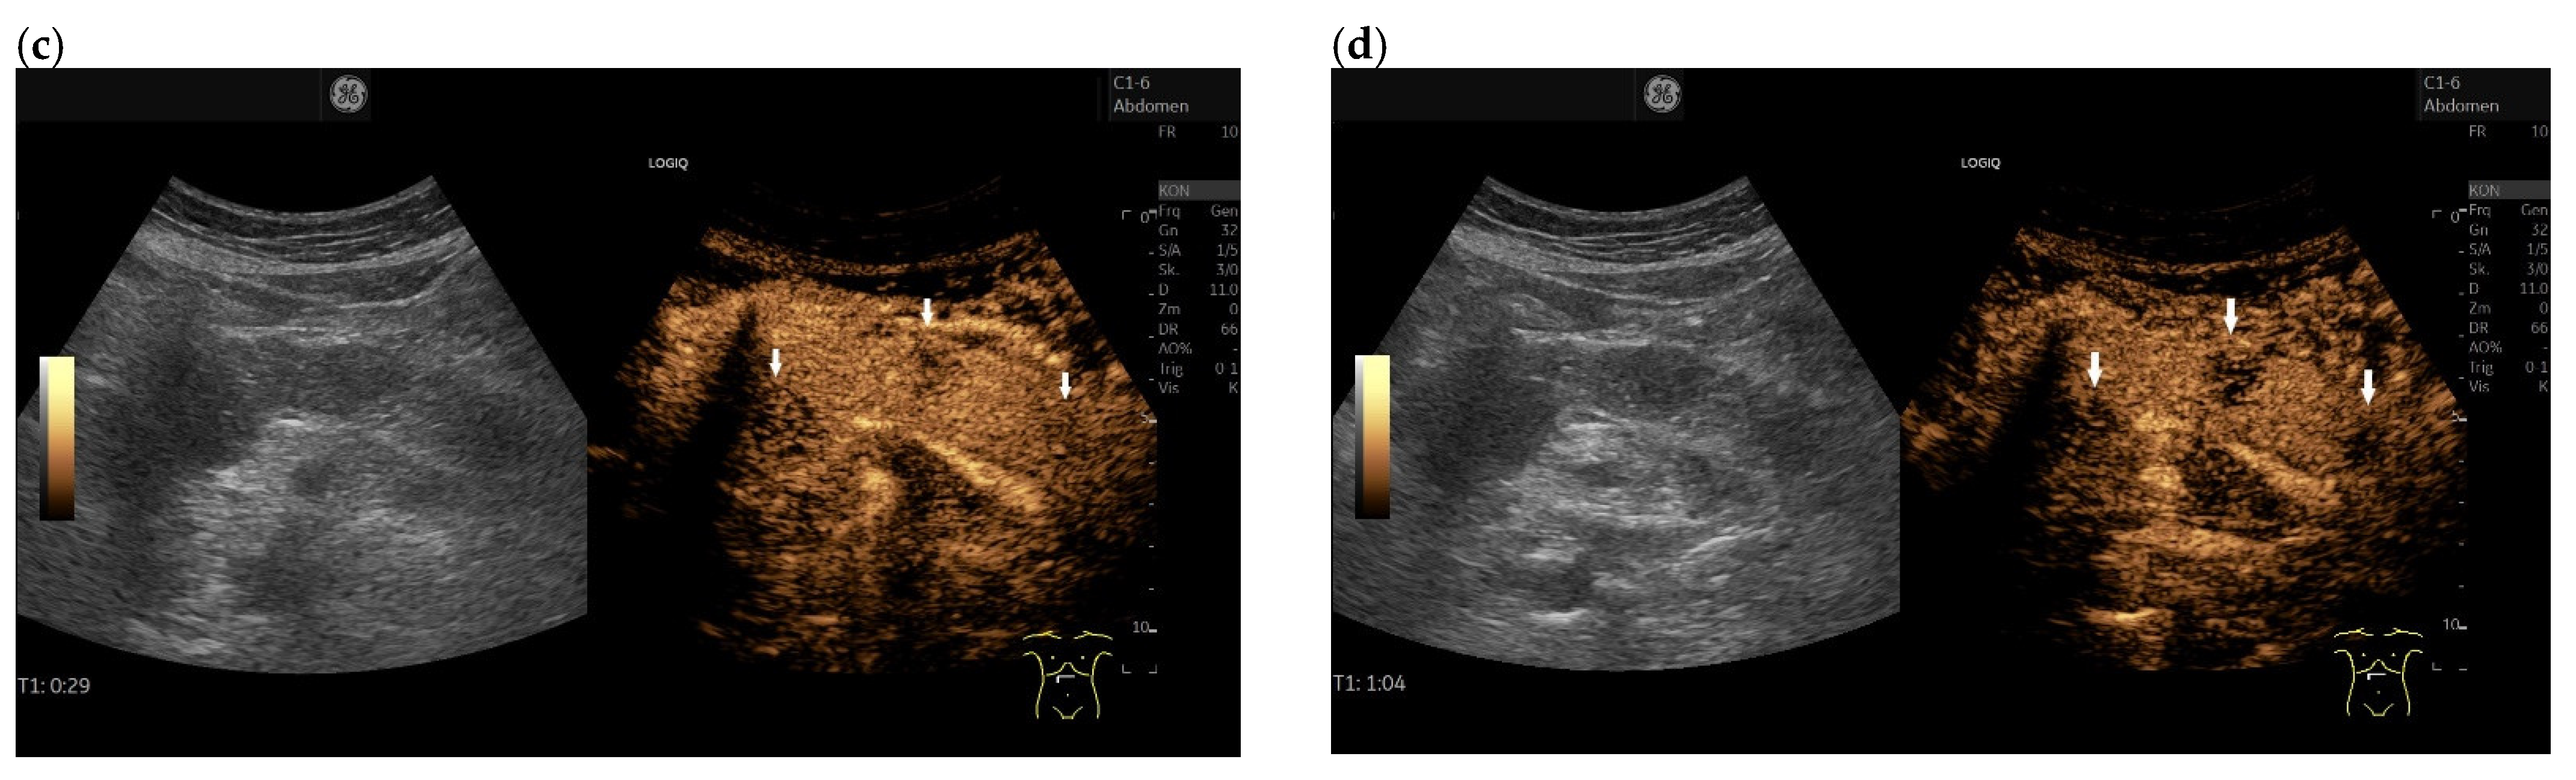

3.4. CEUS and CH-EUS

| Cases | CEUS | CH-EUS | ||

|---|---|---|---|---|

| Arterial Phase | Venous Phase | Arterial Phase | Venous Phase | |

| RCC metastases [83] (n = 4) | Hyperenhancement, Early | Hyperenhancement | ||

| RCC metastases [61] (n = 3) | Hyperenhancement, homogeneous pattern | Slow washout | ||

| RCC metastasis [86] (n = 1) | Hyperenhancement, Inhomogeneous pattern | No washout | ||

| Melanoma metastasis [63] (n = 1) | Iso- to slightly hypoenhanced | Hypoenhanced | ||

| Melanoma metastasis [87] (n = 1) | Isoenhanced | Hypoenhancement of the peripheral rim, central non-enhancement | ||

| Melanoma metastasis [61] (n = 1) | Isoenhanced, heterogeneous | Fast washout | ||

| SCLC metastasis [83] (n = 1) | Hyperenhancement | Rapid washout | ||

| Breast, ovarian, colon metastases, sarcoma metastases [61] (n = 6) | Hypoenhancement, homogeneous or heterogeneous | Fast or slow washout | ||

| Lymphoma metastasis [61] (n = 1) | Hyperenhancement, homogeneous pattern | Fast washout |